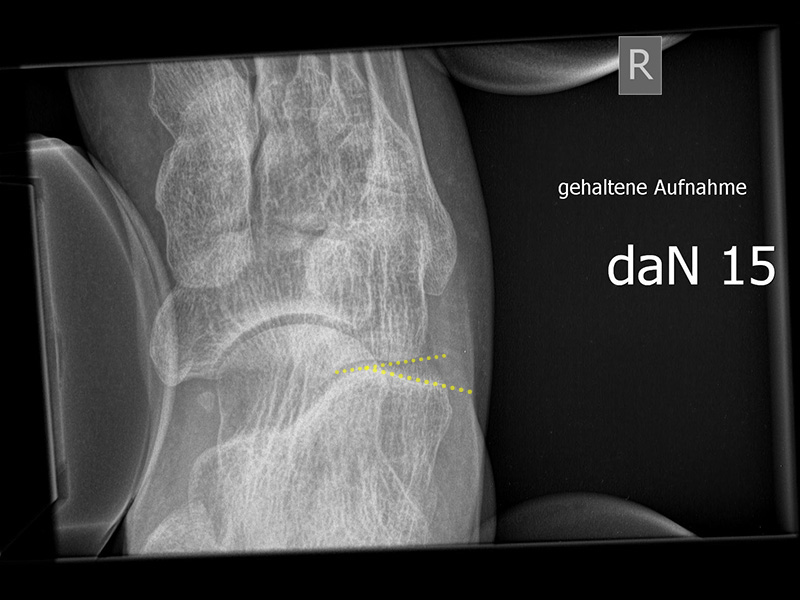

Stressaufnahme des oberen Sprunggelenks ap

Positionierung:

• Patient in Rückenlage auf dem Röntgentisch. Ferse auf der Röntgenkassette liegend (Achse des oberen Sprunggelenks parallel zur Röntgenkassette).

• Film horizontal auf dem Röntgentisch.

• Zentralstrahl mittig auf das obere Sprunggelenk fokussiert.

• Röntgenröhre 0° vertikal.

• Der Fuß liegt in der Haltevorrichtung (z.  Telos-Gerät, Scheuba-Apparat). Die Ferse wird von lateral stabilisiert, die Halterung ermöglicht ein Kippen des Rückfußes.

• Von medial wird über die Tibia ein kontrollierter Druck von bis zu 15 daN (Dekanewton, entspricht ca. 15 kg) aufgebaut.

Kennzeichen des Röntgenbildes:

• ap Abbildung des oberen Sprunggelenks.

• Beurteilung der lateralen Aufklappbarkeit.

• Subfibularer Raum mit ggf. Ossikeln einsehbar.

• Als pathologisch gelten laterale Aufklappbarkeit > 10° im Seitenvergleich oder Unterschied im Abstand zwischen der lateralen, distalen Taluskante zur Fibulagelenkfläche > 3 mm.

Besondere Bemerkungen zum Beispielbild:

• Abbildung des oberen Sprunggelenks ap.

• Laterale Aufklappbarkeit.

• Degenerative Veränderungen sichtbar mit knöchernen Anbauten am Innenknöchel.